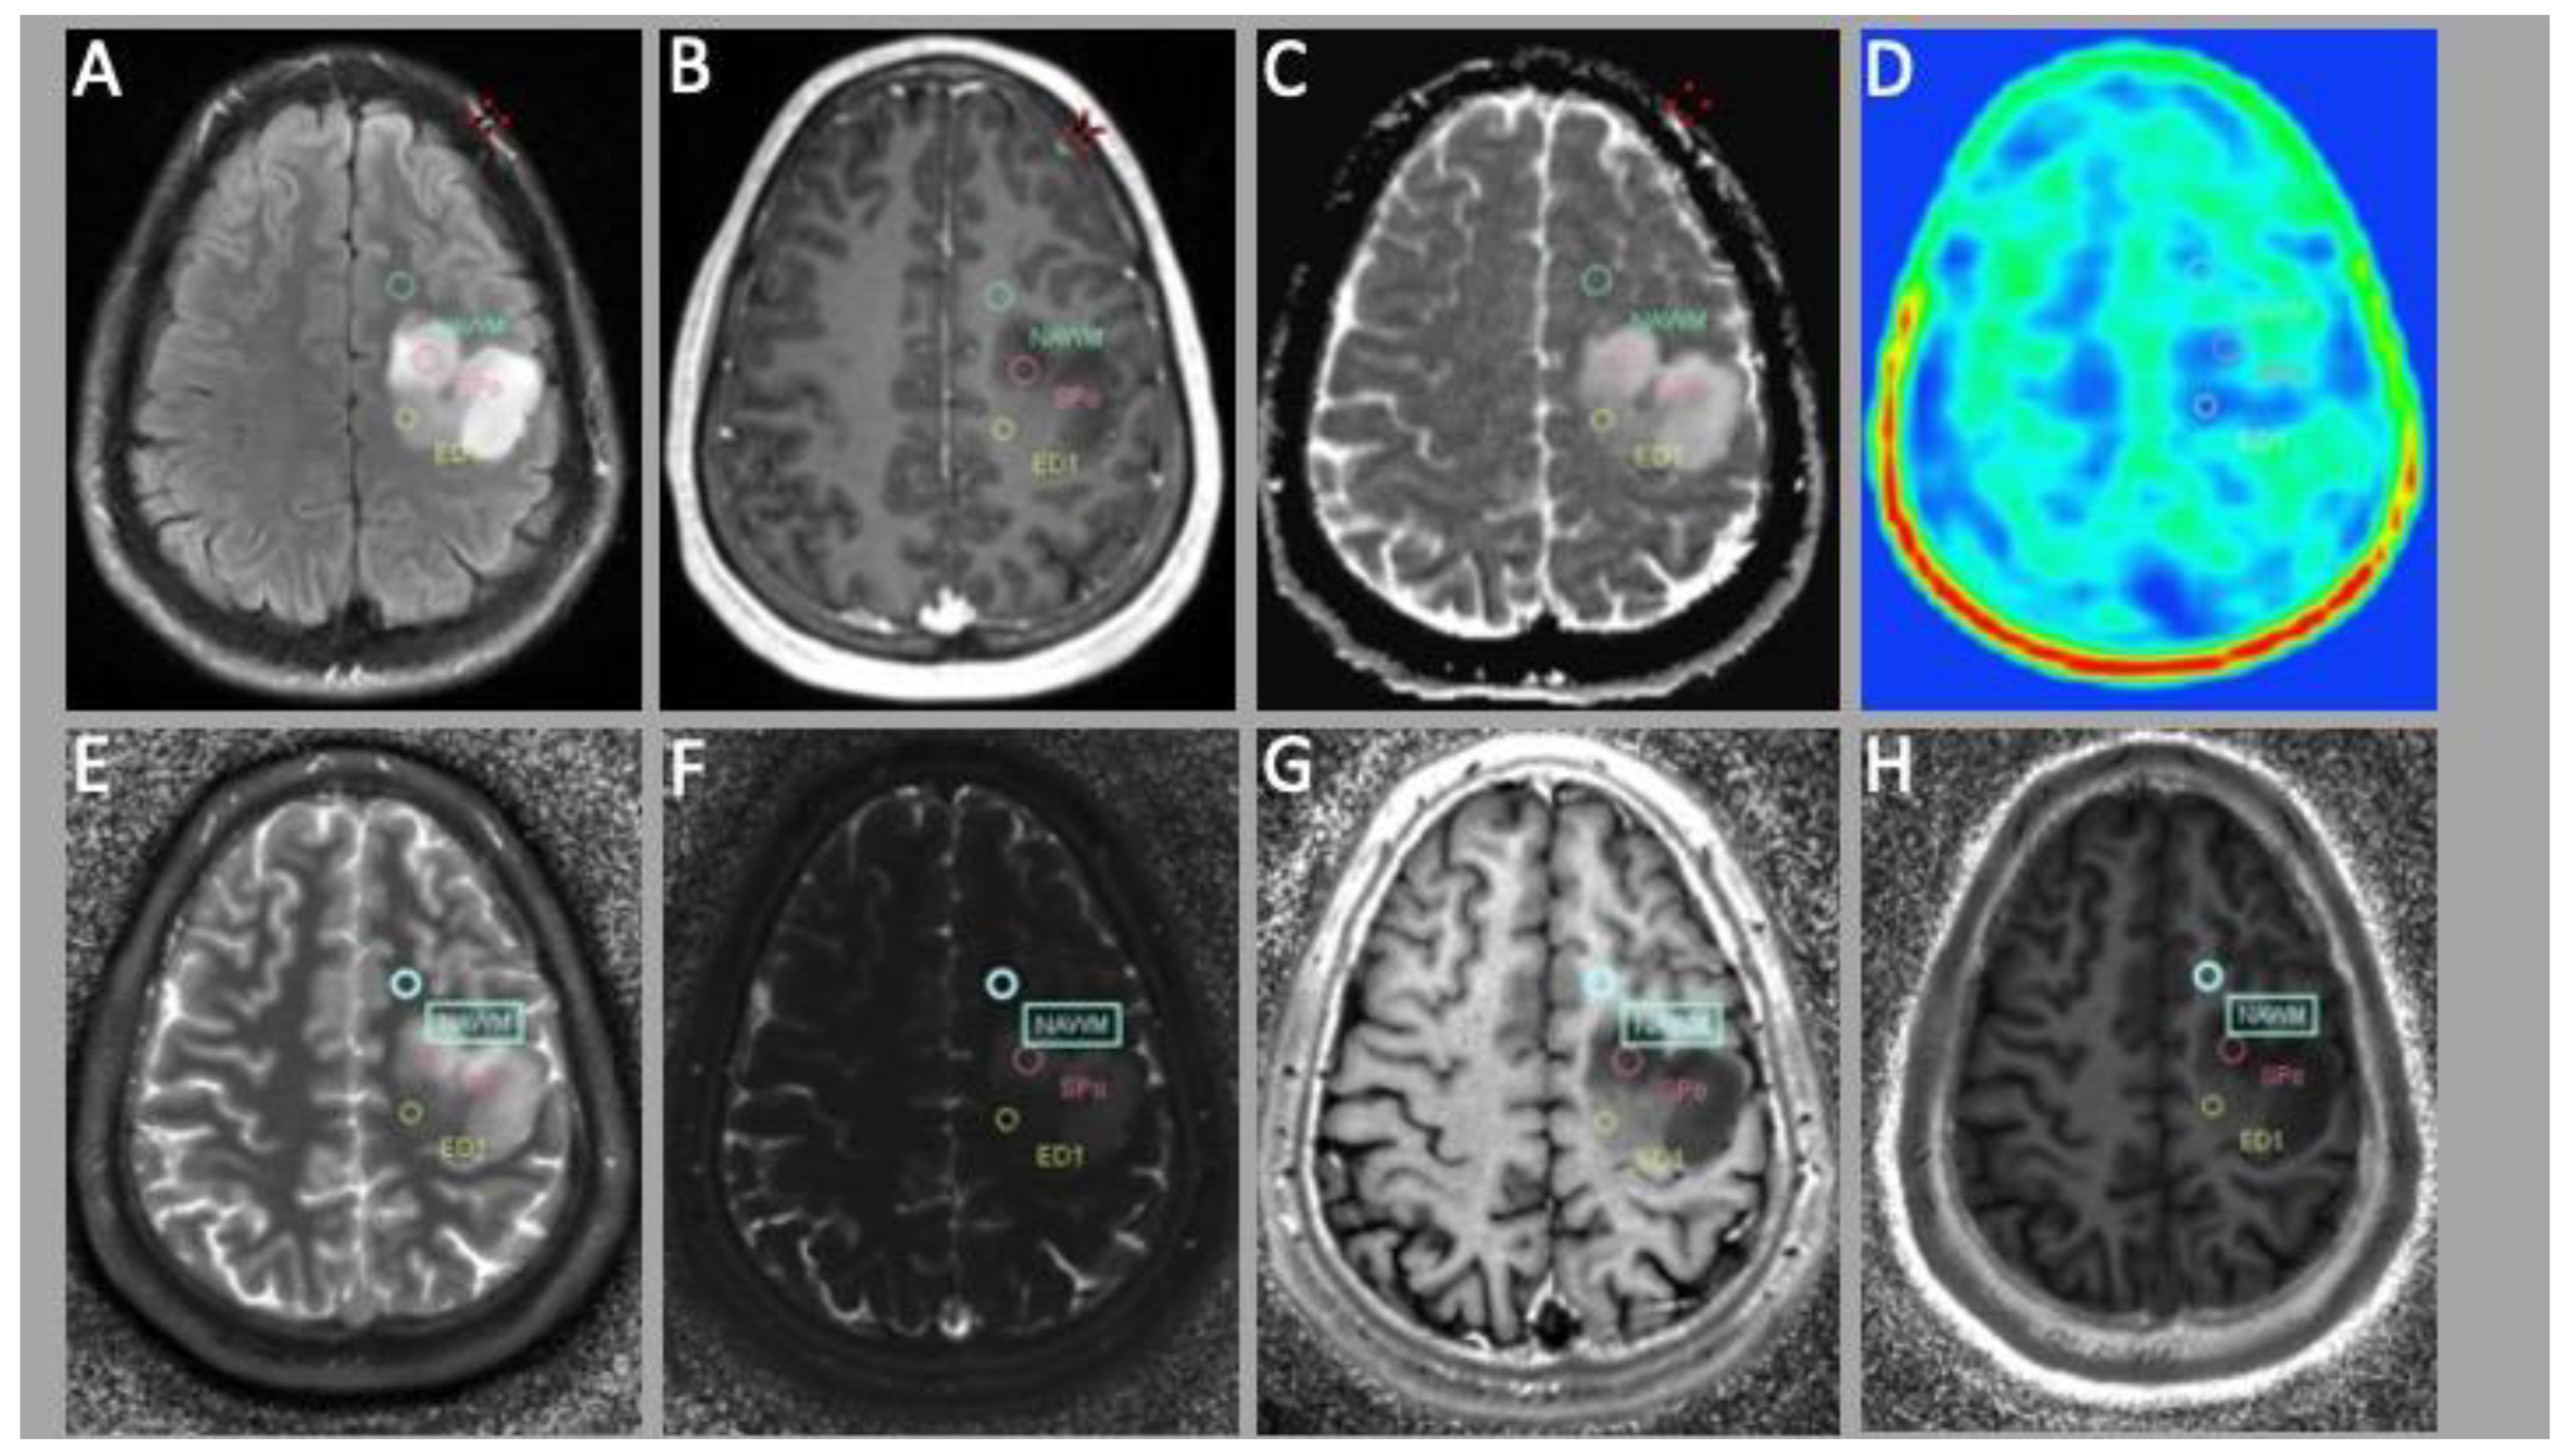

3.1. MRF

3.2. PET Evaluation

3.3. Correlation of MRF and PET